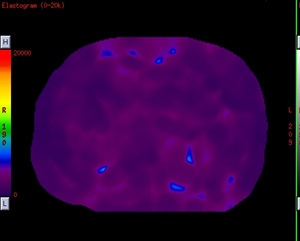

MR-Touch is a Phase Contrast (PC) application that generates an image contrast related to the shear stiffness of soft tissue. MR-Touch is a single touch application that sensitively images the propagation characteristics of acoustic shear waves generated in the tissue of interest. A liver exam is an example of where the application is used.

MR-Touch is performed by synchronizing the Gradient Echo (1.5T pulse sequence used) used with acoustic waves that are applied with an external MR-Touch Device. The pulse sequence is modified with an oscillating Motion Encoding Gradient (MEG). The external acoustic driver is triggered by the PSD so that the MEG is synchronized with the external acoustic wave. The duration of the MEG is the same as the period of the mechanical vibration. A phase shift occurs in the MR signal, which correlates with the mechanical excursion. An algorithm is used to derive a relative stiffness map and wave images from the phase images.

MR-Touch acquisition generates the following image types: magnitude, phase maps, wave maps. Six relative stiffness images are reconstructed for each slice location. The relative stiffness images are reconstructed in color and grey scale, and in masked and un-masked versions. Mask portion is depicted as a checkerboard pattern on the image. It is created to identify regions that should not be included in ROI measurements.